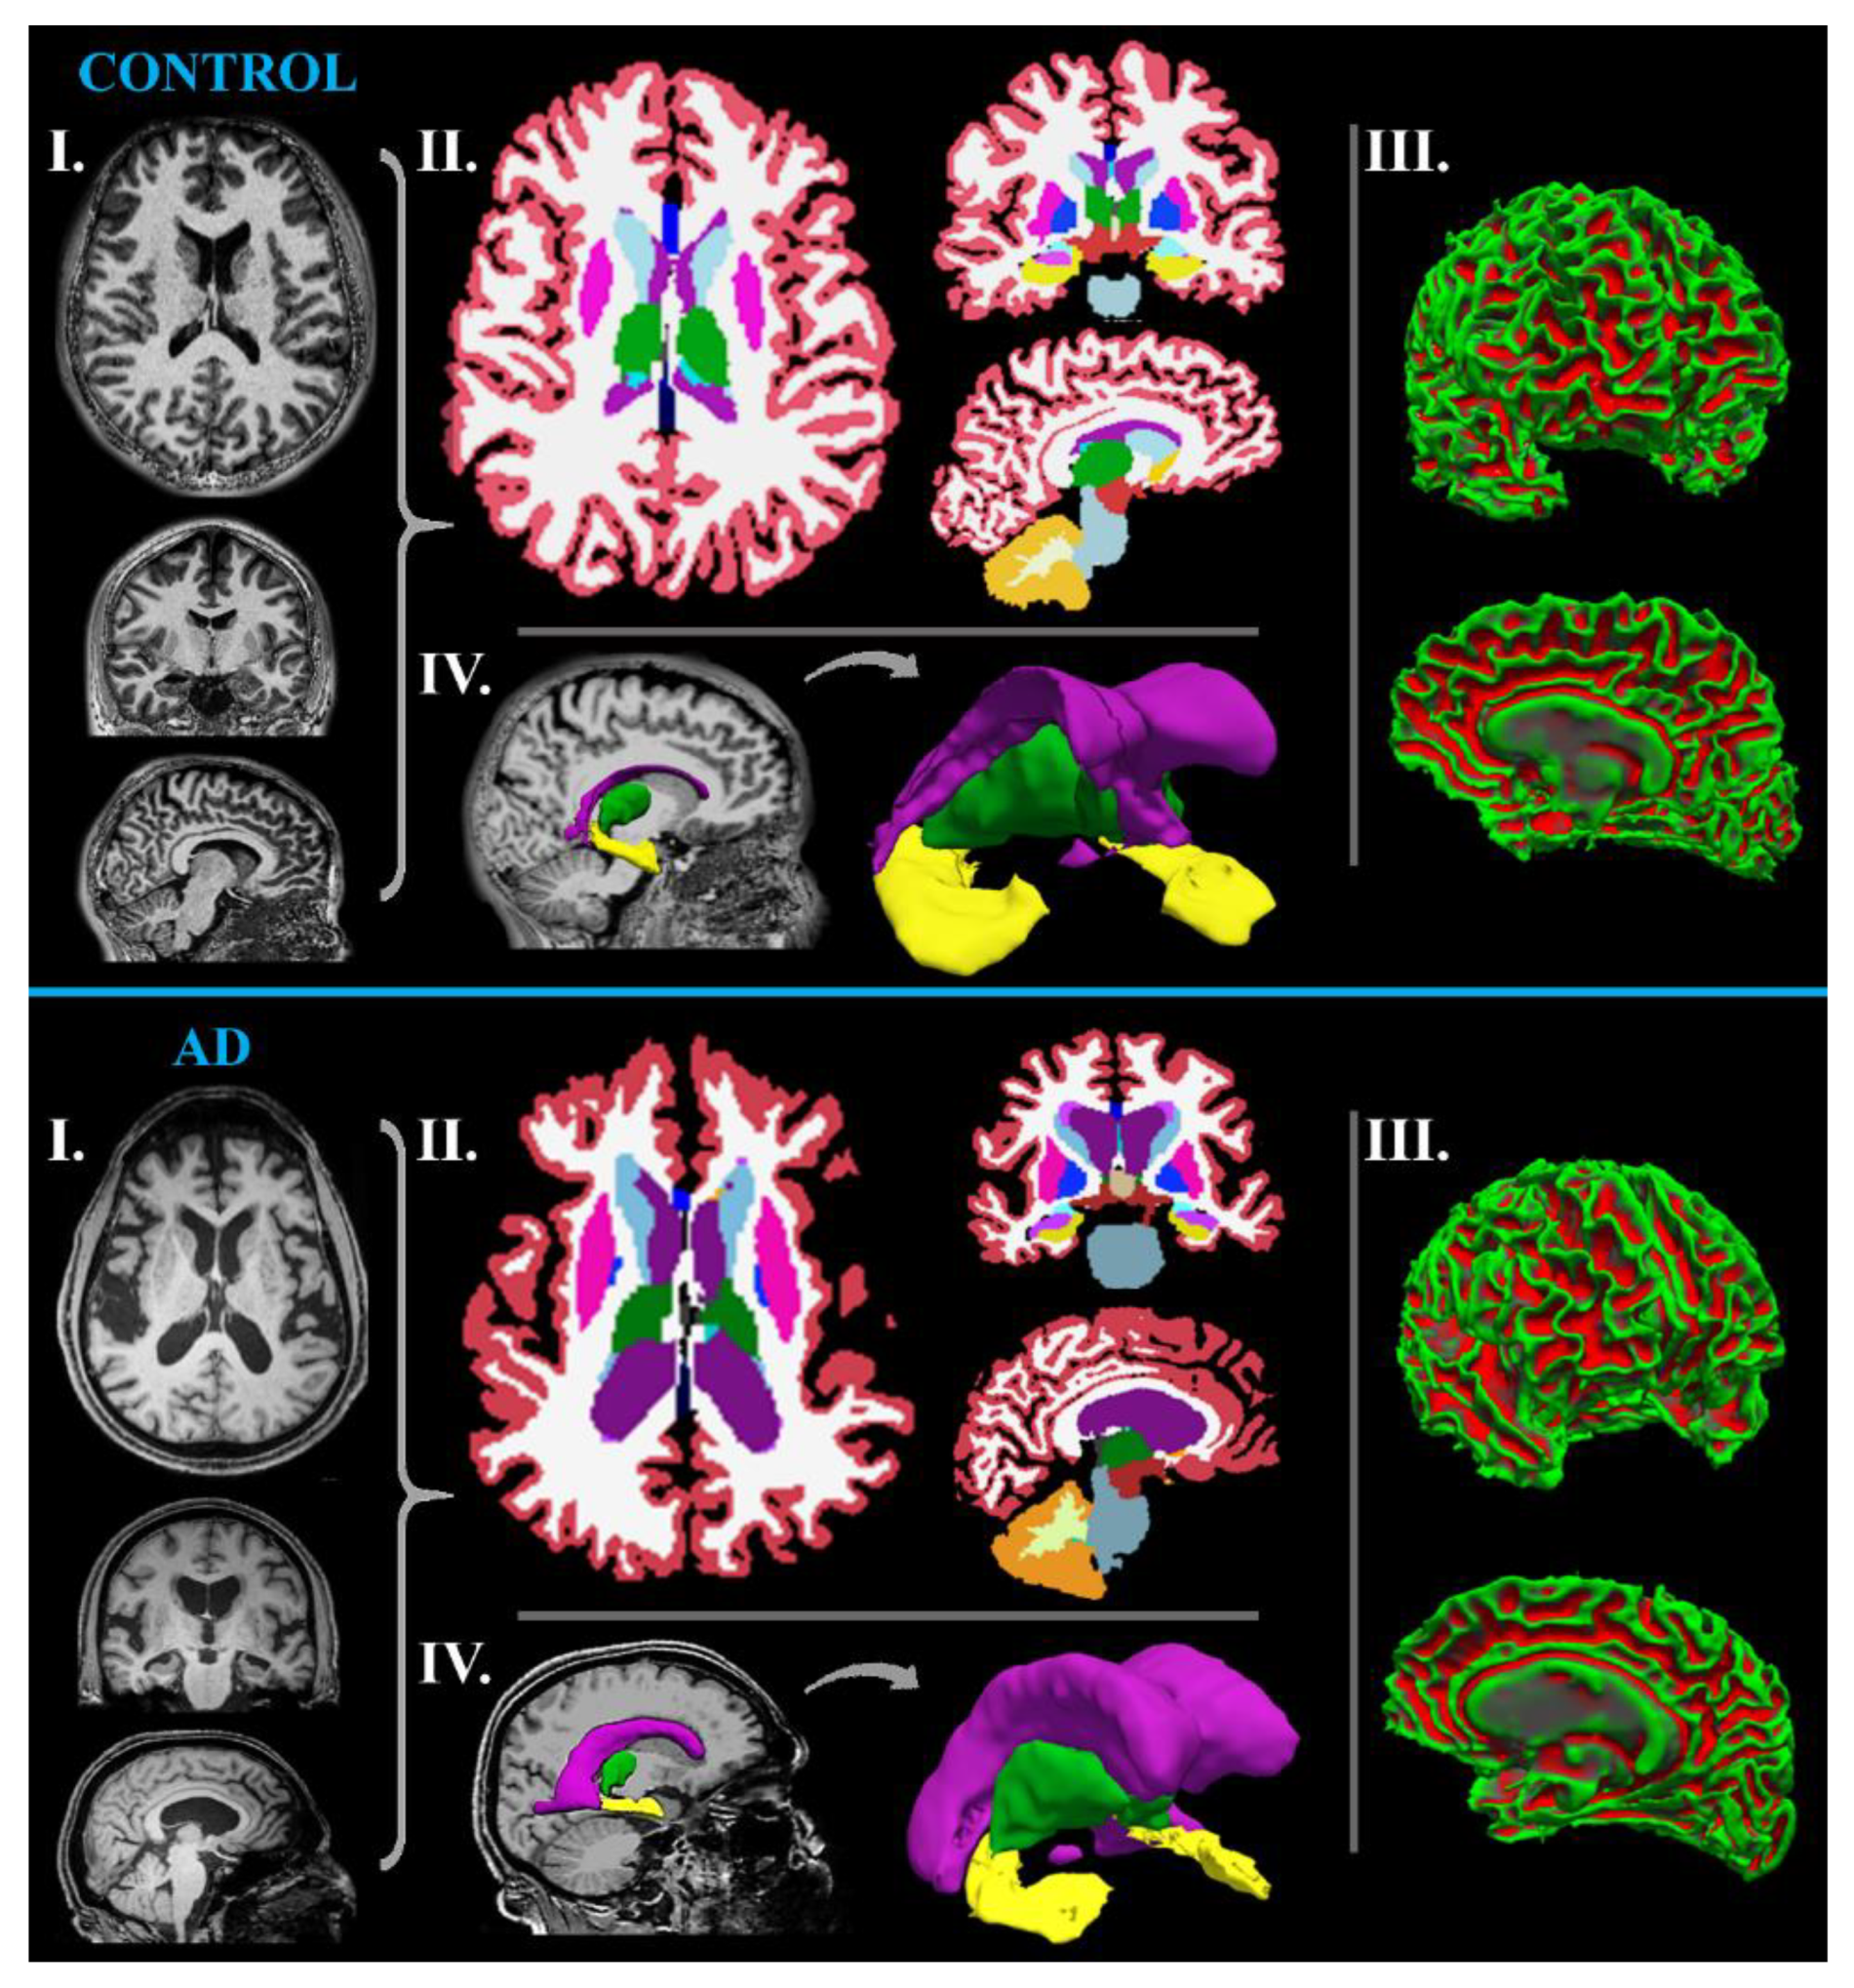

MR-Volumetry

- Chandra, A.; Dervenoulas, G.; Politis, M.; Alzheimer’s Disease Neuroimaging, I. Magnetic resonance imaging in Alzheimer’s disease and mild cognitive impairment. J. Neurol. 2019, 266, 1293–1302. [Google Scholar] [CrossRef] [PubMed]

- Desikan, R.S.; Cabral, H.J.; Hess, C.P.; Dillon, W.P.; Glastonbury, C.M.; Weiner, M.W.; Schmansky, N.J.; Greve, D.N.; Salat, D.H.; Buckner, R.L.; et al. Automated MRI measures identify individuals with mild cognitive impairment and Alzheimer’s disease. Brain 2009, 132, 2048–2057. [Google Scholar] [CrossRef]

| MR-volumetry | sensitive tissue volume changes | several non-standardized softwares |